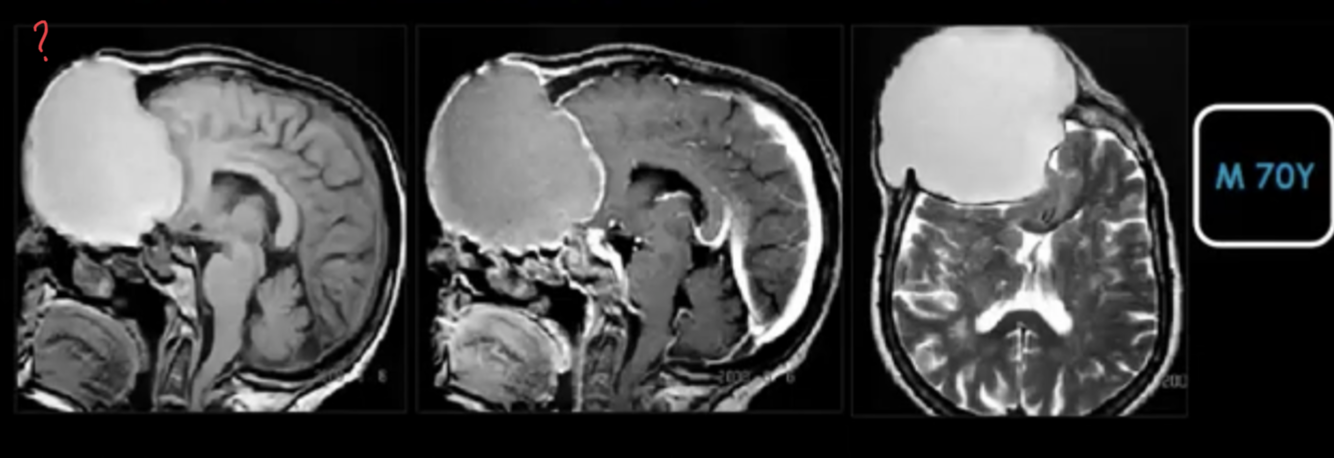

Description and dx?